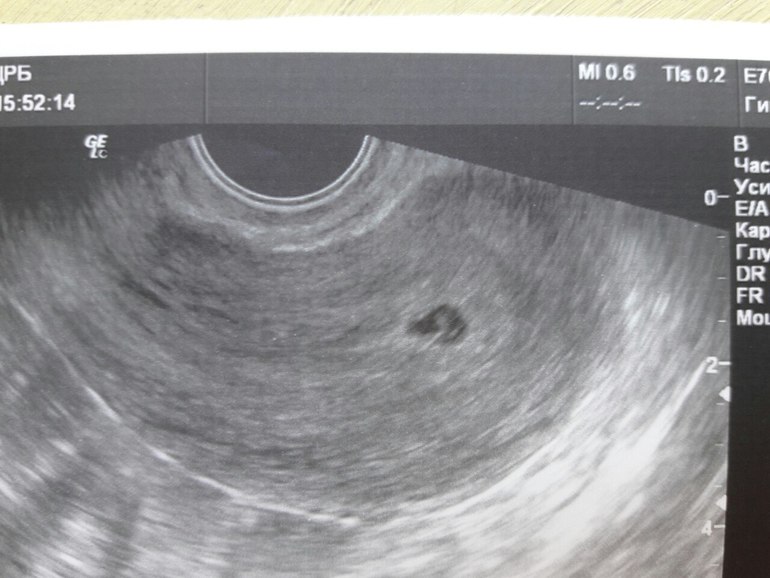

На узи пошла по МС в 6 недель. Врач посмотрела и ничего плохого не увидела. Но почему случился выкидыш?Уже через пару часов пошла кровь...девочки,вы понимаете что-нибудь в этих снимках?!Отслойка,гематома?Что здесь видно?!

Видно плодное яйцо и всё, на таким сроке плаценты ещё не существует. Скорей всего была какая-то проблема, может спонтанная генетическая мутация. И может конечно я ошибаюсь, не профи, но плодное яйцо кажется мне размытым и не чётким, обычно оно имеет чёткие очертание и на УЗИ выглядит почти чёрным.

На УЗИ плодное яйцо. Всё. На таком сроке НЕТ и не может быть плаценты. Отслаиваться просто не чему.Не отчаивайтесь. Возьмите себя в руки. Обязательно пройдите обследование особенно на инфекции. В ближайшие 6мес МИНИМУМ беременеть нельзя.Природа умнее нас.Возможно были какие-то проблемы у Вас ,у него не важно. Было бы страшнее и хуже если бы это произошло в 20нед.Теперь всё нужно планировать:вылечить кариес,исключить инфекции(тот же хламидиоз к примеру). Правильно питаться. Категорически исключить никотин и алкоголь(и папой и мамой)Одно точно само УЗИ и осмотр на кресле не могут вызвать выкидыш.Удачи. И не зацикливайтесь. Это не трагедия,это печальное событие. Там не было ребенка,там была оплодотворенная яйцеклетка.